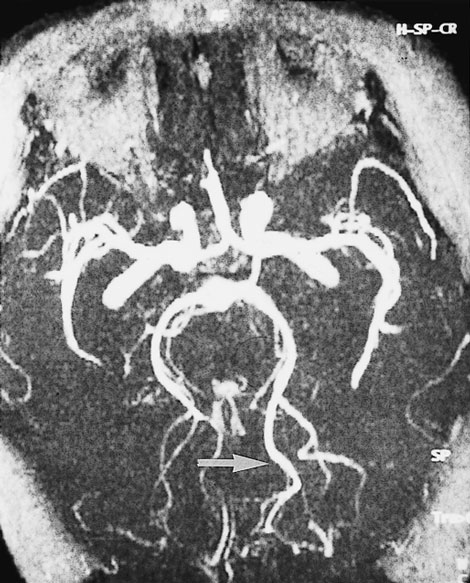

Computed tomography (CT) brain scan was performed three hours after the completion of coronary angiography. No additional contrast was used. The CT brain scan (Box 1) showed marked bilateral contrast enhancement of the occipital lobes and no evidence of a cerebral haemorrhage. Intravenous heparin treatment was commenced. By the following day, she was able to see shapes and shadows but had persistent headache and nausea. A repeat CT brain scan did not show any residual abnormality. During the next 48 hours, her vision progressively returned. She described flashing lights in her right eye and had evidence of right homonymous hemianopia. Magnetic resonance imaging (MRI) showed increased signals in the grey matter of the medial aspect of the left occipital lobe, on a background of longstanding mild ischaemic changes consistent with her age and cardiac risk factors (Box 2A). Magnetic resonance angiography (MRA) showed patency of both posterior cerebral arteries, with dilatation of branches supplying the left occipital lobe (Box 2B). Heparin therapy was ceased, as there was no evidence of acute thromboembolism or acute infarction. She fully regained her vision five days after coronary angiography.

These mechanisms seem possible in our patient, and they were supported by the results of imaging studies. There were bilateral occipital lobe changes when she had clinical cortical blindness (Box 1), representing oedema and passage of contrast across the blood–brain barrier. Cortical blindness is synonymous with bilateral homonymous hemianopia from involvement of the occipital cortex.1 When our patient was recovering and exhibiting right homonymous hemianopia, there were MRI changes in the left occipital gyrus, and differences in the calibre of the vessels on the two sides (Box 2).

2: Magnetic resonance imaging (MRI) of the patient's head 48 hours after coronary angiography, when she had right homonymous hemianopia

B: A magnetic resonance angiogram (MRA) at the same time shows that both posterior cerebral arteries are patent. The peripheral branches on the left side are larger (arrow).